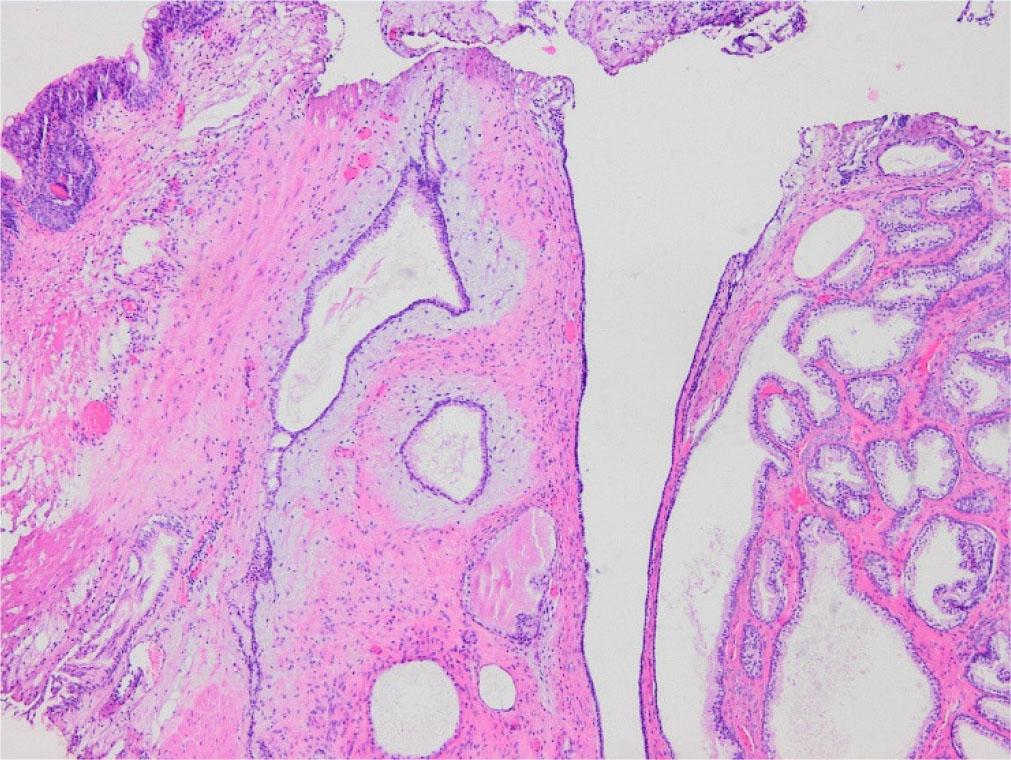

Fig. 1a and 1b -